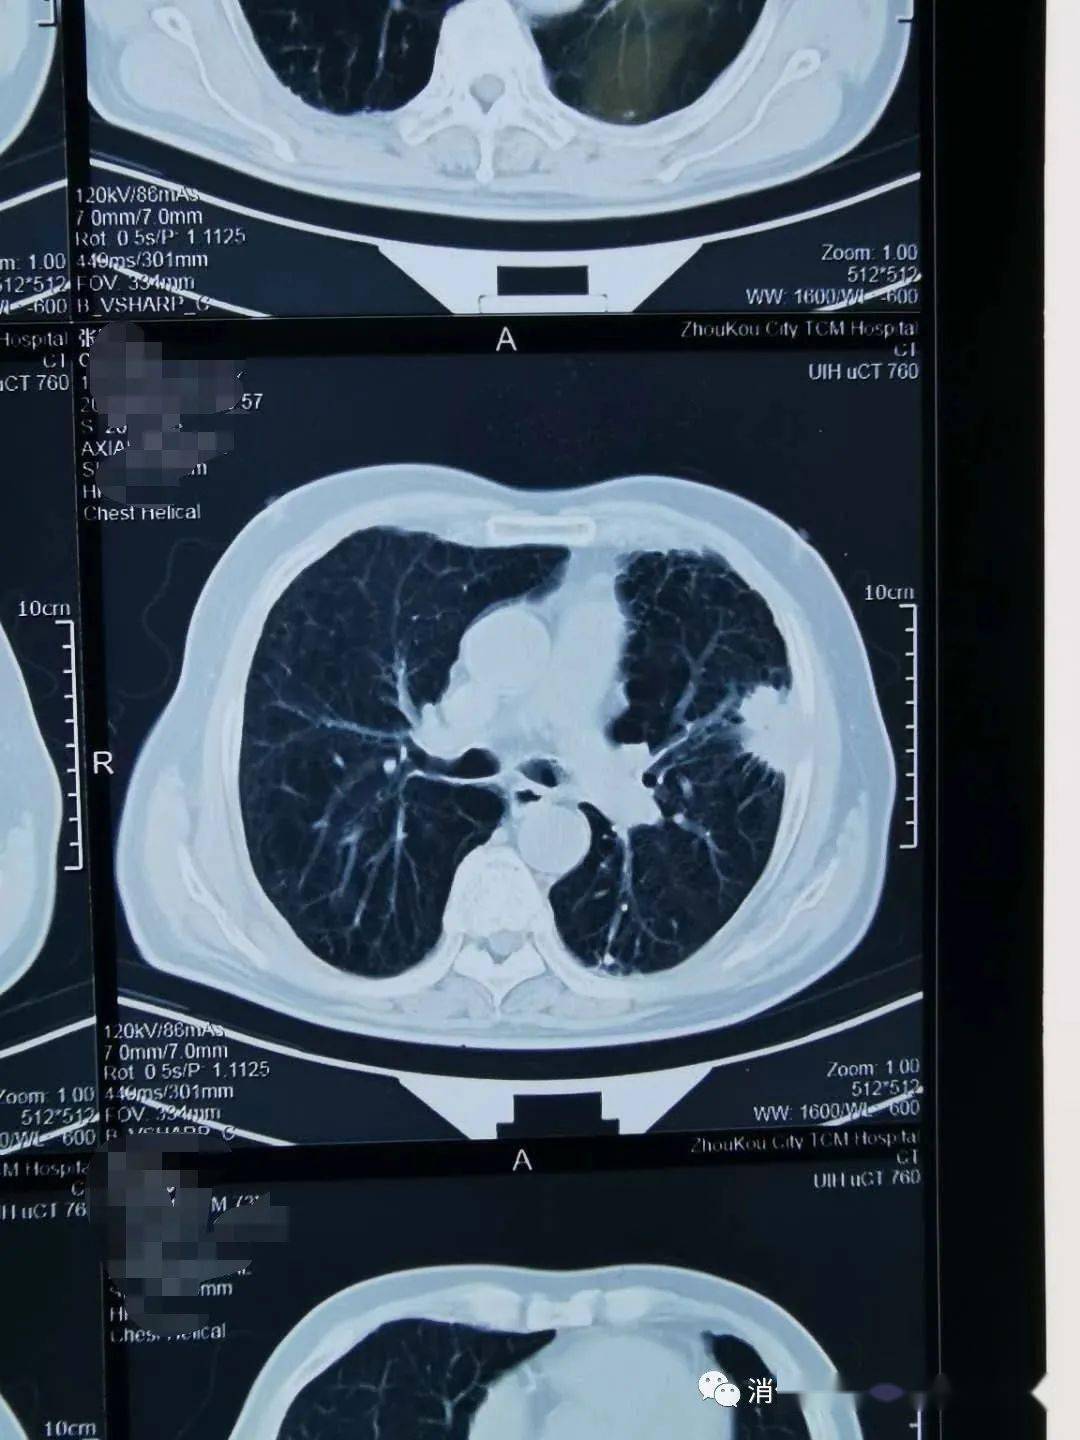

左肺癌脑转移,左肺肿瘤穿刺活检证实为小细胞内分泌癌,脑转移伽 - 抖

图片尺寸788x788